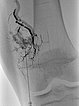

Über den Mikrokatheter wird jetzt selektiv mit Ethylen-Vinyl-Alkohol-Kopolymer embolisiert, das sich in den feinen Fisteln verteilt.

In der Röntgenübersichtsaufnahme nach Embolisation der Fisteln zeigt sich der selektive Ausguss der Fisteln mit dem röntgendichten Embolisat (Cast).